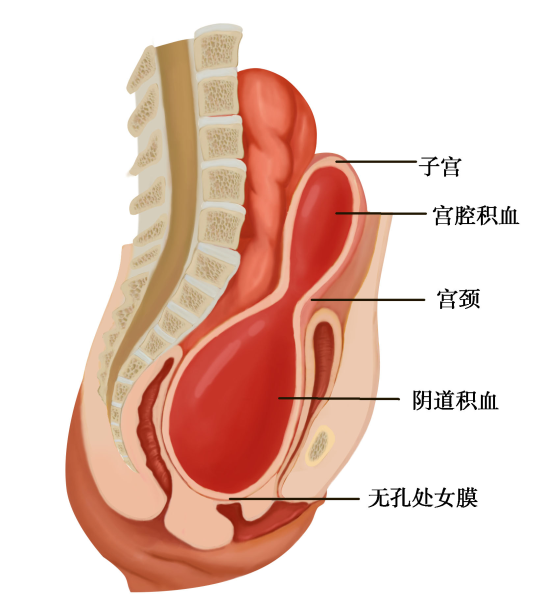

外生殖器异常最常见的是处女膜闭锁(imperforate hymen),又称无孔处女膜。系发育过程中,阴道末端的泌尿生殖窦组织未腔化所致。由于处女膜无孔,故阴道分泌物或月经初潮的经血排出受阻积聚在阴道内。有时经血可经输卵管逆流至腹腔。若不及时切开,反复多次的月经来潮使积血增多发展为子宫腔、输卵管和盆腔积血,输卵管可因积血粘连而致伞端闭锁,经血逆流至盆腔易发生子宫内膜异位症。少部分处女膜发育异常可表现小孔的筛孔处女膜和纵隔处女膜。

图22-1 处女膜闭锁并阴道、宫腔积血

绝大多数患者至青春期发生周期性下腹坠痛,进行性加剧。严重者可引起肛门胀痛和尿频等症状。检查可见处女膜膨出,表面呈紫蓝色;肛诊可扣及盆腔囊性包块。偶有幼女因大量黏液潴留在阴道内,导致处女膜向外凸出、下腹坠痛而就诊。盆腔超声检查可见阴道内有积液。确诊后应及时手术治疗。先用粗针穿刺处女膜中部膨隆部,抽出陈日积血后再进行“X”形切开,排出积血;常规检查宫颈是否正常,切除多余的处女膜,修剪处女膜,再用可吸收缝线缝合切口边缘。